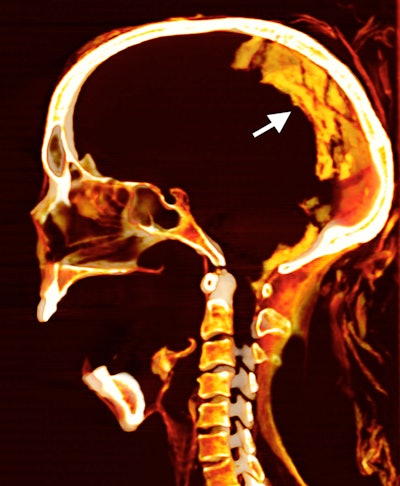

CT shows the brain inside the skull of the "Screaming Woman" mummy.